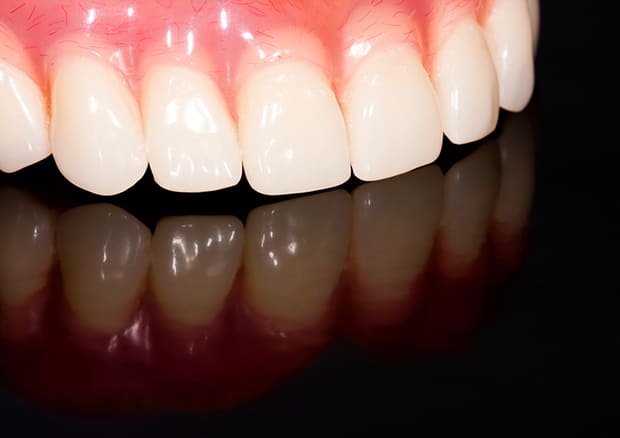

- ノンクラスプデンチャー

右下の歯が割れているとのことでご来院された患者様です。全身疾患も考慮し、目立たない入れ歯を相談して決定し、大変満足いただけました。